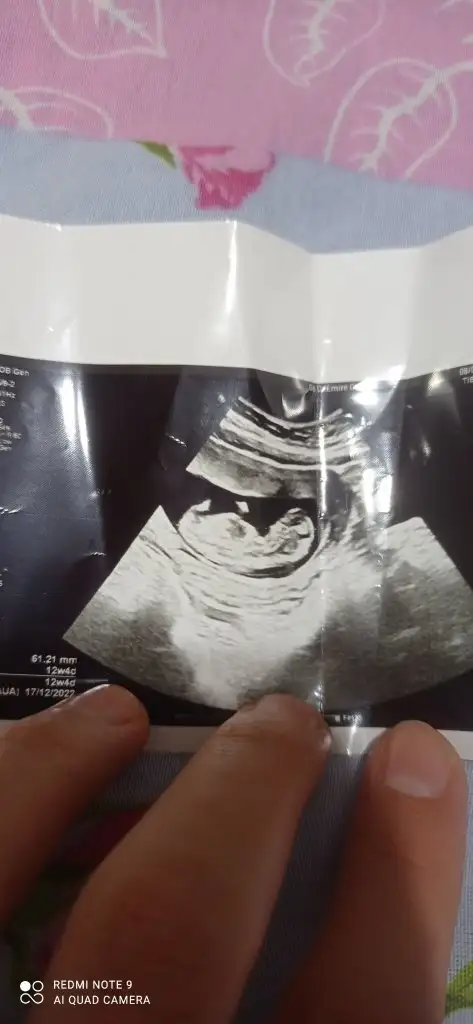

paşa gibi12+ 5 çok heyecanlıyım

Karnımdan ultarsyon hayırlı ve sağlıklı olsun tabiki ama gönlümüzden erkek geçiyor rabbim hayırlısını nasip etsinpaşa gibi